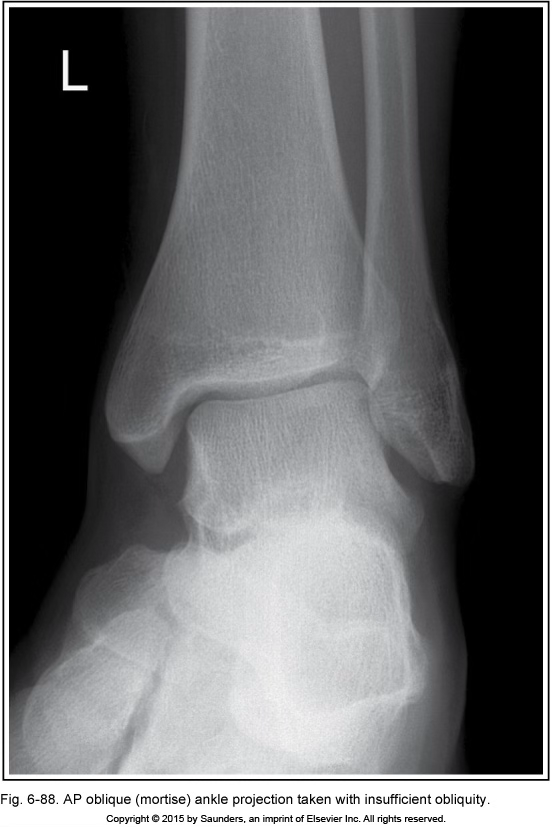

AP ankle oblique (mortise)

insufficient obliquity